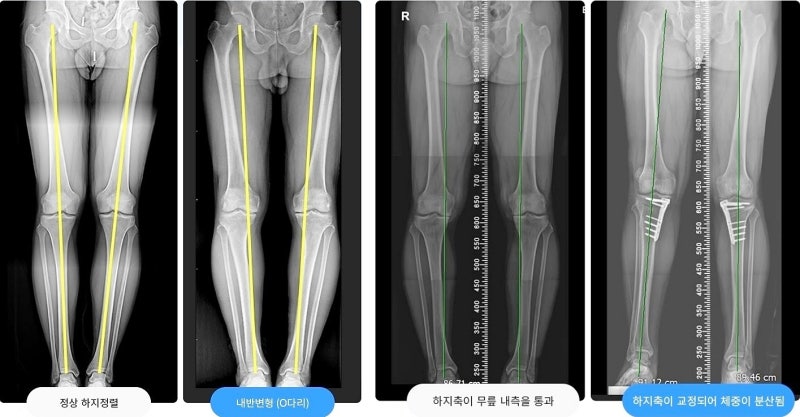

관절염은 주로 무릎 안쪽에서 진행되며 다리의 축이 비스듬해지면서 이른바 ‘O다리’가 된다. 축이 곧지 않으면 체중을 균등하게 분산시키는 뼈의 무게를 늘리는데 노화 또는 사고로 인해 축이 무너지게 되면서 연골이 닳는 속도는 빨라지고, 즉 관절염 진행 속도가 빨라지는 것이다. 근위골절골술 수술 과정

관절염은 주로 무릎 안쪽에서 진행되며 다리의 축이 비스듬해지면서 이른바 ‘O다리’가 된다. 축이 곧지 않으면 체중을 균등하게 분산시키는 뼈의 무게를 늘리는데 노화 또는 사고로 인해 축이 무너지게 되면서 연골이 닳는 속도는 빨라지고, 즉 관절염 진행 속도가 빨라지는 것이다. 근위골절골술 수술 과정근위경골절골술의 수술 과정 설명은 꽤 간단하다.경골근위부를 절골하여 다리의 축이 ‘일자형’이 되도록 적합한 정도의 공간을 열어 뼈 모양을 교정시킨다.(왼쪽 그림) 그 후에 행해진 각도에 금속판을 이용하여 견고하게 고정하고 뼈의 유합 촉진을 위해 뼈 이식을 실시한다. (오른쪽 그림) 빈 공간 속 뼈가 생성되면서 일반 다리로 회복되는데 설정한 각도에 따라 다리 축을 변경하는 것이다. 오다리교정술이 필요한 경우 (굽은 다리교정술 조건)휜 다리 교정술(근위 경 골절술)에는 몇가지 조건이 있다.나는 중기 관절염이다.초기 관절염은 약물, 이학 요법을 쓰는 말기 관절염의 경우는 무릎 연골이 다 닳아 바꿀 경우이다.휜 다리 교정술은 초기와 말기 사이의 중기, 연골이 아직 있을 때 가능하다.내 발은 내 반 변형이다.O다리 시게루형에 의해서 안쪽 연골의 마모가 심해축이 변형된 사람의 때에 적당한 수술이다.저의 안쪽 외 관절(밖)는 아직 괜찮다.안쪽 관절염이 진행되고 O다리에 커지며 이때 교정 수술을 하는데 이때 외측은 문제가 있어서는 안 된다.저는 관절염이 비교적 일찍 시작한.100세 때 라키에 관절염이 비교적 일찍 시작, 향후의 관절을 보존하고 싶은 사람 50~60세의 나이가 적당하다.나는 두 다리를 더 자유롭게 사용하고 싶다.말기 관절염이 되면 인공 관절을 대체하게 되지만 인공 관절들은 아무래도 불편이 있다.그러나 오다리 교정술의 경우, 핀을 꽂아, 뼈 자체를 새로 생성시키고 핀을 제거하기 때문에 최종적으로는 자신의 관절을 보존한다.그래서 불편이 없다, 보다 활동적인 생활을 보낼 수 있다.줄기 세포 이식술 동시 수술이 가능(연쇄 시스템)근위경골절술을 진행하면서 마모된 관절에 줄기세포를 도포해 연골 스스로 재생할 수 있도록 하면 시너지 효과가 더 커진다. ※줄기세포이식술(카테스템) 줄기세포이식술은 재생효과가 좋은 아기의 제대혈에서 나온 혈액인 제대혈에서 유래한 줄기세포를 다량 함유한 치료제를 손상된 연골에 발라 연골재생을 유도하는 수술이다. 근위경 골절술 재활근위경골절골술은 절골 부위가 골유합(골생성)돼야 완전한 체중부하보행이 가능하다. 수술 후 1~2일째부터 바로 목발 보행을 시작한다. 수술 후 6주간 목발 및 보조기 사용이 필요하다. 수술 후 812주 후부터 가벼운 운동 복귀가 가능하다. 모든 과정은 최소 3개월 정도의 시간이 필요한 수술이다.이 과정 중 뼈가 물고기가 되는 것이 가장 중요하므로 이를 혈관 수축 효과가 있는 담배는 절대 금물이다. 서울원병원만의 구부러진 다리교정술의 특별함(가장 중요)특허받은 한국형 근위경골절술용 금속판 개발의 휘어진 다리교정술에 사용되던 기존 금속판은 서양인 체형에 따라 개발돼 한국인 체형에는 맞지 않고 이물감 및 통증이 남는 경우가 많았다. 이영민 서울원병원 대표원장은 이를 보완해 서울대병원 정형외과 의료진과의 공동연구로 한국인 체형에 맞는 금속판을 개발해 보다 만족스러운 수술 결과를 얻게 됐다.근위경 골절술 분야에 대한 끊임없는 연구서울원병원 나영곤 대표원장은 사체실험을 통한 근위경 골절술 연구의 우수성을 인정받아 국제학술지 논문 게재와 함께 서울대 의과대학 박사학위를 취득하고 다수의 관련 논문을 국제학술지(SCI)에 발표했다.수술을 할 수 있는 조건을 충족하는 사람이 근위경골절술을 통해 축을 수정해 관절염 촉진을 막을 수 있다고 한다.또한 이 수술을 통해 오다리가 일직선 다리로 예쁘게 자라기 때문에 다리 길이도 1cm 내외로 늘어나는 미용 효과도 얻을 수 있다는 점은 참고하기 바란다.나영곤 원장의 굽은 다리 교정술 유튜브 링크와 함께, 이제 근위경 골절술 포스팅 종료! https://youtu.be/cFl05f1PIm8#서울원병원 #근위경골절골술 #구부러진다리교정 #오다리교정 #카테스템 #강서구근위경골절골술 #강서구오다리교정 #강서구카티스템#연골재생#무릎줄기세포#강서구성형외과#화곡역정형외과#무릎통증#무릎수술#오다리교정비용#구부러진다리교정비용 #오다리교정수술비용